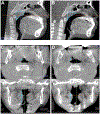

Materials and methods: In this retrospective cohort study, a total of 60 pediatric patients (mean age: 8.00, range: 5-15, 32 females and 28 males) who had tonsillar hypertrophy (size 3 and 4) were included and divided into the control group (n = 20) and expansion group (n = 40). The control group did not undergo any treatment. The expansion group underwent RPE using a conventional Hyrax expander, activated 0.25 mm per day for 4-6 weeks. Final CBCT scans (T2) were performed 13.8 ± 6.5 months after the initial scan (T1). Pediatric sleep questionnaire (PSQ) and BMI were obtained at each timepoint. Volumetric analysis of adenoid and palatine tonsils was performed using a combination of bony and soft tissue landmarks in CBCT scans through Anatomage Invivo 6 imaging software. Paired t-tests were used to evaluate the difference between the initial and final adenoid and tonsil volumes. p values less than 0.05 were considered statistically significant.

Results: Compared to the control group, the expansion group experienced a statistically significant decrease in both adenoid and tonsil volume. There was non-statistically significant increase in volume from T1 to T2 for the control group. For the expansion group, 90.0% and 97.5% of patients experienced significant reduction in adenoid and tonsil volume, respectively. The average volume decrease of adenoids was 16.8% while that of tonsils was 38.5%. The patients had up to 51.6% and 75.4% reduction in adenoid and tonsil size, respectively, following RPE orthodontic treatment. Pearson correlation ranged from 0.88 to 0.99 for each measurement, representing excellent internal consistency. There was a significant reduction in the PSQ scores from 5.81 ± 3.31 to 3.75 ± 2.38 in expansion group (p < 0.001).